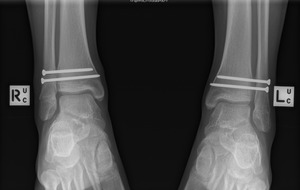

Both ankles demonstrated widening of the syndesmosis intervals when Cotton stress test was applied (Figure 1 and 2). The ankles were reduced under image intensifier and each ankle had definitive percutaneous fixation using two 3.5mm cortical screws (Synthes). Postoperatively, the patient remained non-weightbearing for 6 weeks. He was allowed to weight-bear as tolerated after 6 weeks in bilateral CAM boots and commenced gentle range of motion exercises with a physiotherapist. Radiographs at 3-months indicated enlocated and stable ankle joints with no failure of syndesmotic fixation (Figure 3). The patient underwent hardware removal and further external rotation stress tests at 3 months. There was no widening of either syndesmosis intervals. The patient progressed well with physiotherapy and was able to return to competitive basketball within 4 weeks of hardware removal. At 16 weeks after the index injury, the patient was able to achieve 30-degree flexion and 45-degree extension of both ankles and VAS pain score was 0 for both ankles at time of follow-up.